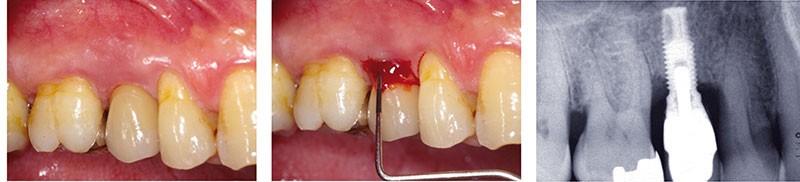

Les péri-implantites sont des maladies inflammatoires d’origine infectieuse qui se manifestent cliniquement par une inflammation des tissus mous, avec un saignement au sondage et/ou parfois une suppuration, ainsi qu’une perte d’attache et une profondeur de poche au sondage supérieure à 5 mm. Radiographiquement, cet état se manifeste par l’existence d’une perte osseuse, correspondant à une exposition de plusieurs spires de l’implant (fig. 1).